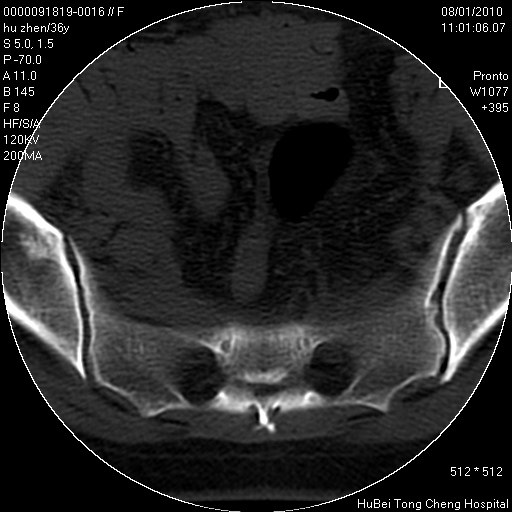

患者 女,36岁。右侧腰腿痛半月余。腰骶椎mr平扫偶然发现骶椎异常信号。

临床诊断:1)腰椎间盘突出症。2)骶椎肿瘤性病变?

骶椎ct平扫(层厚、层距均为5mm),图像如下:

考虑s1骨纤维异常增殖症。